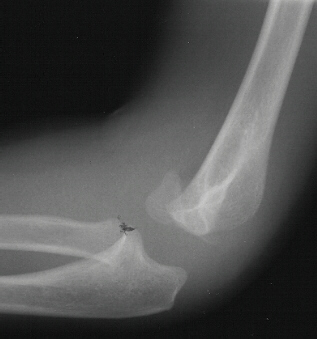

A five year and six month old white male sustained a fall

onto his outstretched right arm with immediate complaints of pain

and swelling in his right elbow. The child was unable to move

his arm secondary to pain. He was on the play ground and the fall

was not witnessed. Physical examination revealed swelling, tenderness

and crepitus over the lateral aspect of the elbow. The skin was

intact and neurovascular examination of the right upper extremity

was without deficits. The patient was taken to the operating room

where under general anesthesia and tourniquet control, the fracture

was exposed utilizing an anterolateral approach. Two diverging

k-wires were placed across the fracture site.